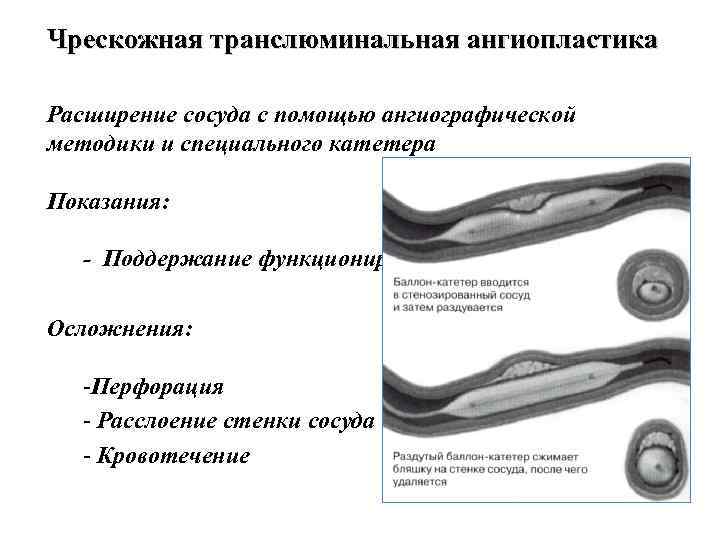

Чрескожная транслюминальная ангиопластика Расширение сосуда с помощью ангиографической методики и специального катетера Показания: - Поддержание функционирования сосуда Осложнения: -Перфорация - Расслоение стенки сосуда - Кровотечение

Чрескожная транслюминальная ангиопластика Расширение сосуда с помощью ангиографической методики и специального катетера Показания: - Поддержание функционирования сосуда Осложнения: -Перфорация - Расслоение стенки сосуда - Кровотечение